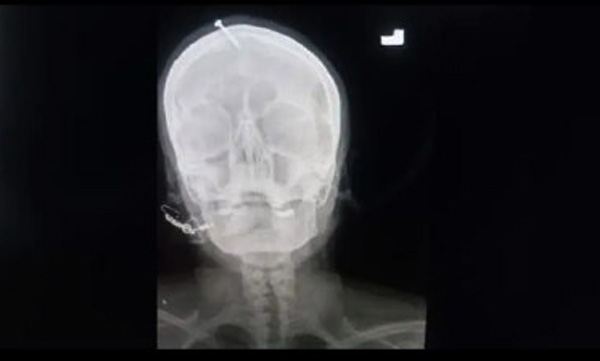

എക്സ്റേ എടുത്തപ്പോഴാണ് തലച്ചോറില് ആണി തുളച്ചു കയറിയതായി മനസ്സിലായത്. തുടര്ന്ന് ഡോക്ടര്മാര് അടിയന്തിര ശസ്ത്രക്രിയ നടത്തി ആണി പുറത്തെടുക്കുകയായിരുന്നു. ആദ്യം യുവതി തന്നെയാണ് ആണി അടിച്ചു കയറ്റിയതെന്നാണ് പറഞ്ഞത്. പിന്നീട് ഇവര് സത്യം പറയുകയായിരുന്നു. മൂന്ന് പെണ്മക്കളുള്ള ഇവര് നാലാമതും ഗര്ഭിണിയായപ്പോള് ഈ കുട്ടി ആണ്കുട്ടിയായിരിയ്ക്കണമെന്ന് ഭര്ത്താവ് നിബന്ധന വെച്ചു. മാത്രമല്ല, നാലാമത്തെ കുട്ടിയും പെണ്കുട്ടി ആയാല് വീട്ടില് നിന്നിറക്കി വിടുകയും വിവാഹ മോചനം ചെയ്യുകയും ചെയ്യുമെന്നും ഭര്ത്താവ് യുവതിയോട് പറഞ്ഞു.